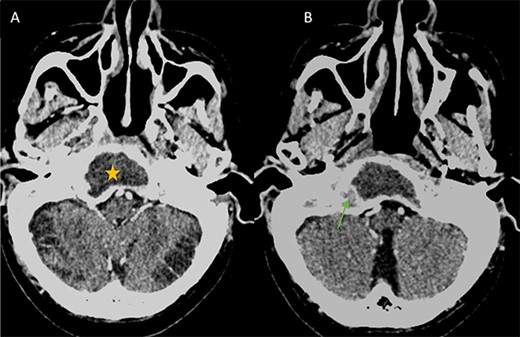

A computed tomography (CT) scan with intravenous contrast was performed (Figs 1 and 2), it revealed:

A 3 × 2.5 × 3.2 cm low-attenuating intra clival mass with peripheral enhancing, accompanied by extensive bone erosion of the clivus.

Bone destruction extending to the petrous, tympanic, and mastoid portions of the temporal bone, with involvement of the body and right greater wing of the sphenoid as well as the occipital bone, and concomitant sequestrum formations within the necrotic bones.

Presence of soft tissue in the middle ear cavity and in the mastoid cells.

(A) Axial CT in soft-tissue window showing an intra clival fluid collection (star). (B) Axial Post contrast CT showing a peripheral enhancement (arrow).